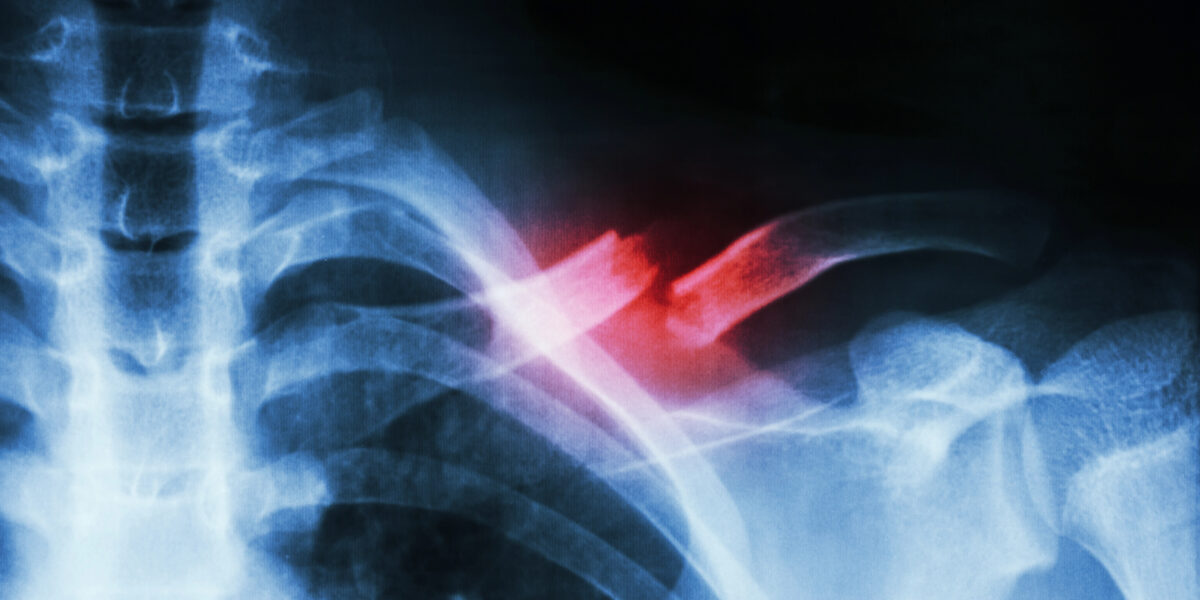

Splitterbruch

Röntgenaufnahme eines Splitterbruchs: Komplexe Verletzungen könnten künftig mit abbaubaren Implantaten schneller und gezielter heilen.

Foto: Smarterpix / stockdevil_666

Ein Bruch am Oberschenkel, eine komplizierte Fraktur am Schädel oder ein Splitterbruch nach einem Unfall: Oft reicht ein Gipsverband. Knochenzellen sind erstaunlich selbstständig – sie bauen den beschädigten Knochen Stück für Stück wieder auf.